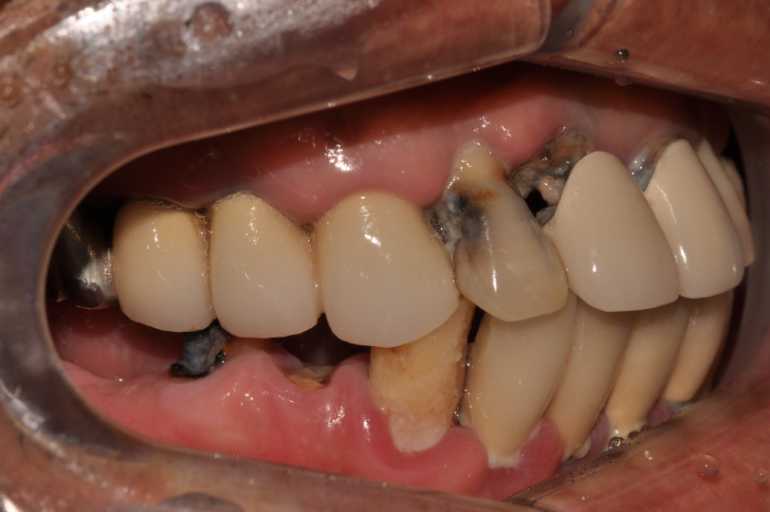

#무치악 임플란트 환자 사례 : 기존 치아의 염증 상태로 인해 치료 시작일 때, 잔존치 전체 발치 + 상악동거상술(양쪽) + 뼈이식다수 + 임플란트 픽스처(뿌리) 17개 식립